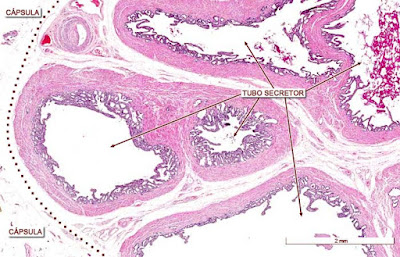

Próstata

Es una glándula alveolar compuesta, la cual es anexa al aparato reproductor y es la mas grande de este, midiendo 4 cm de ancho por 3 cm de largo y con un peso de 20 gramos. Se encuentra rodeando a la uretra en la región en que se une con la vejiga. Se estima que cuenta con entre 40 a 50 adenómeros que se apoyan de una gran cubierta de tejido muscular liso.

Sus adenomeros túbulos alveolares son de gran luz formada por células dispuestas en un epitelio cilíndrico simple a pseudoestratificado según la actividad de la glándula (entre más actividad sexual más pseudoestratificado), junto con tejido conjuntivo laxo y fibras musculares lisas (para contracción y ayudar a la expulsión de espermatozoides). El epitelio puede formar pliegues que invaden la luz llamadas lengüetas prostáticas.

También presenta estructuras redondas llamadas cuerpos amiláceos o concreciones calcarias que presentan afinidad por la eosina. Estas funcionan como un indicador de la actividad de la glándula, entre más haya mayor actividad tendrá la glándula.

![]() |

| Los pliegues son lengüetas prostáticas |